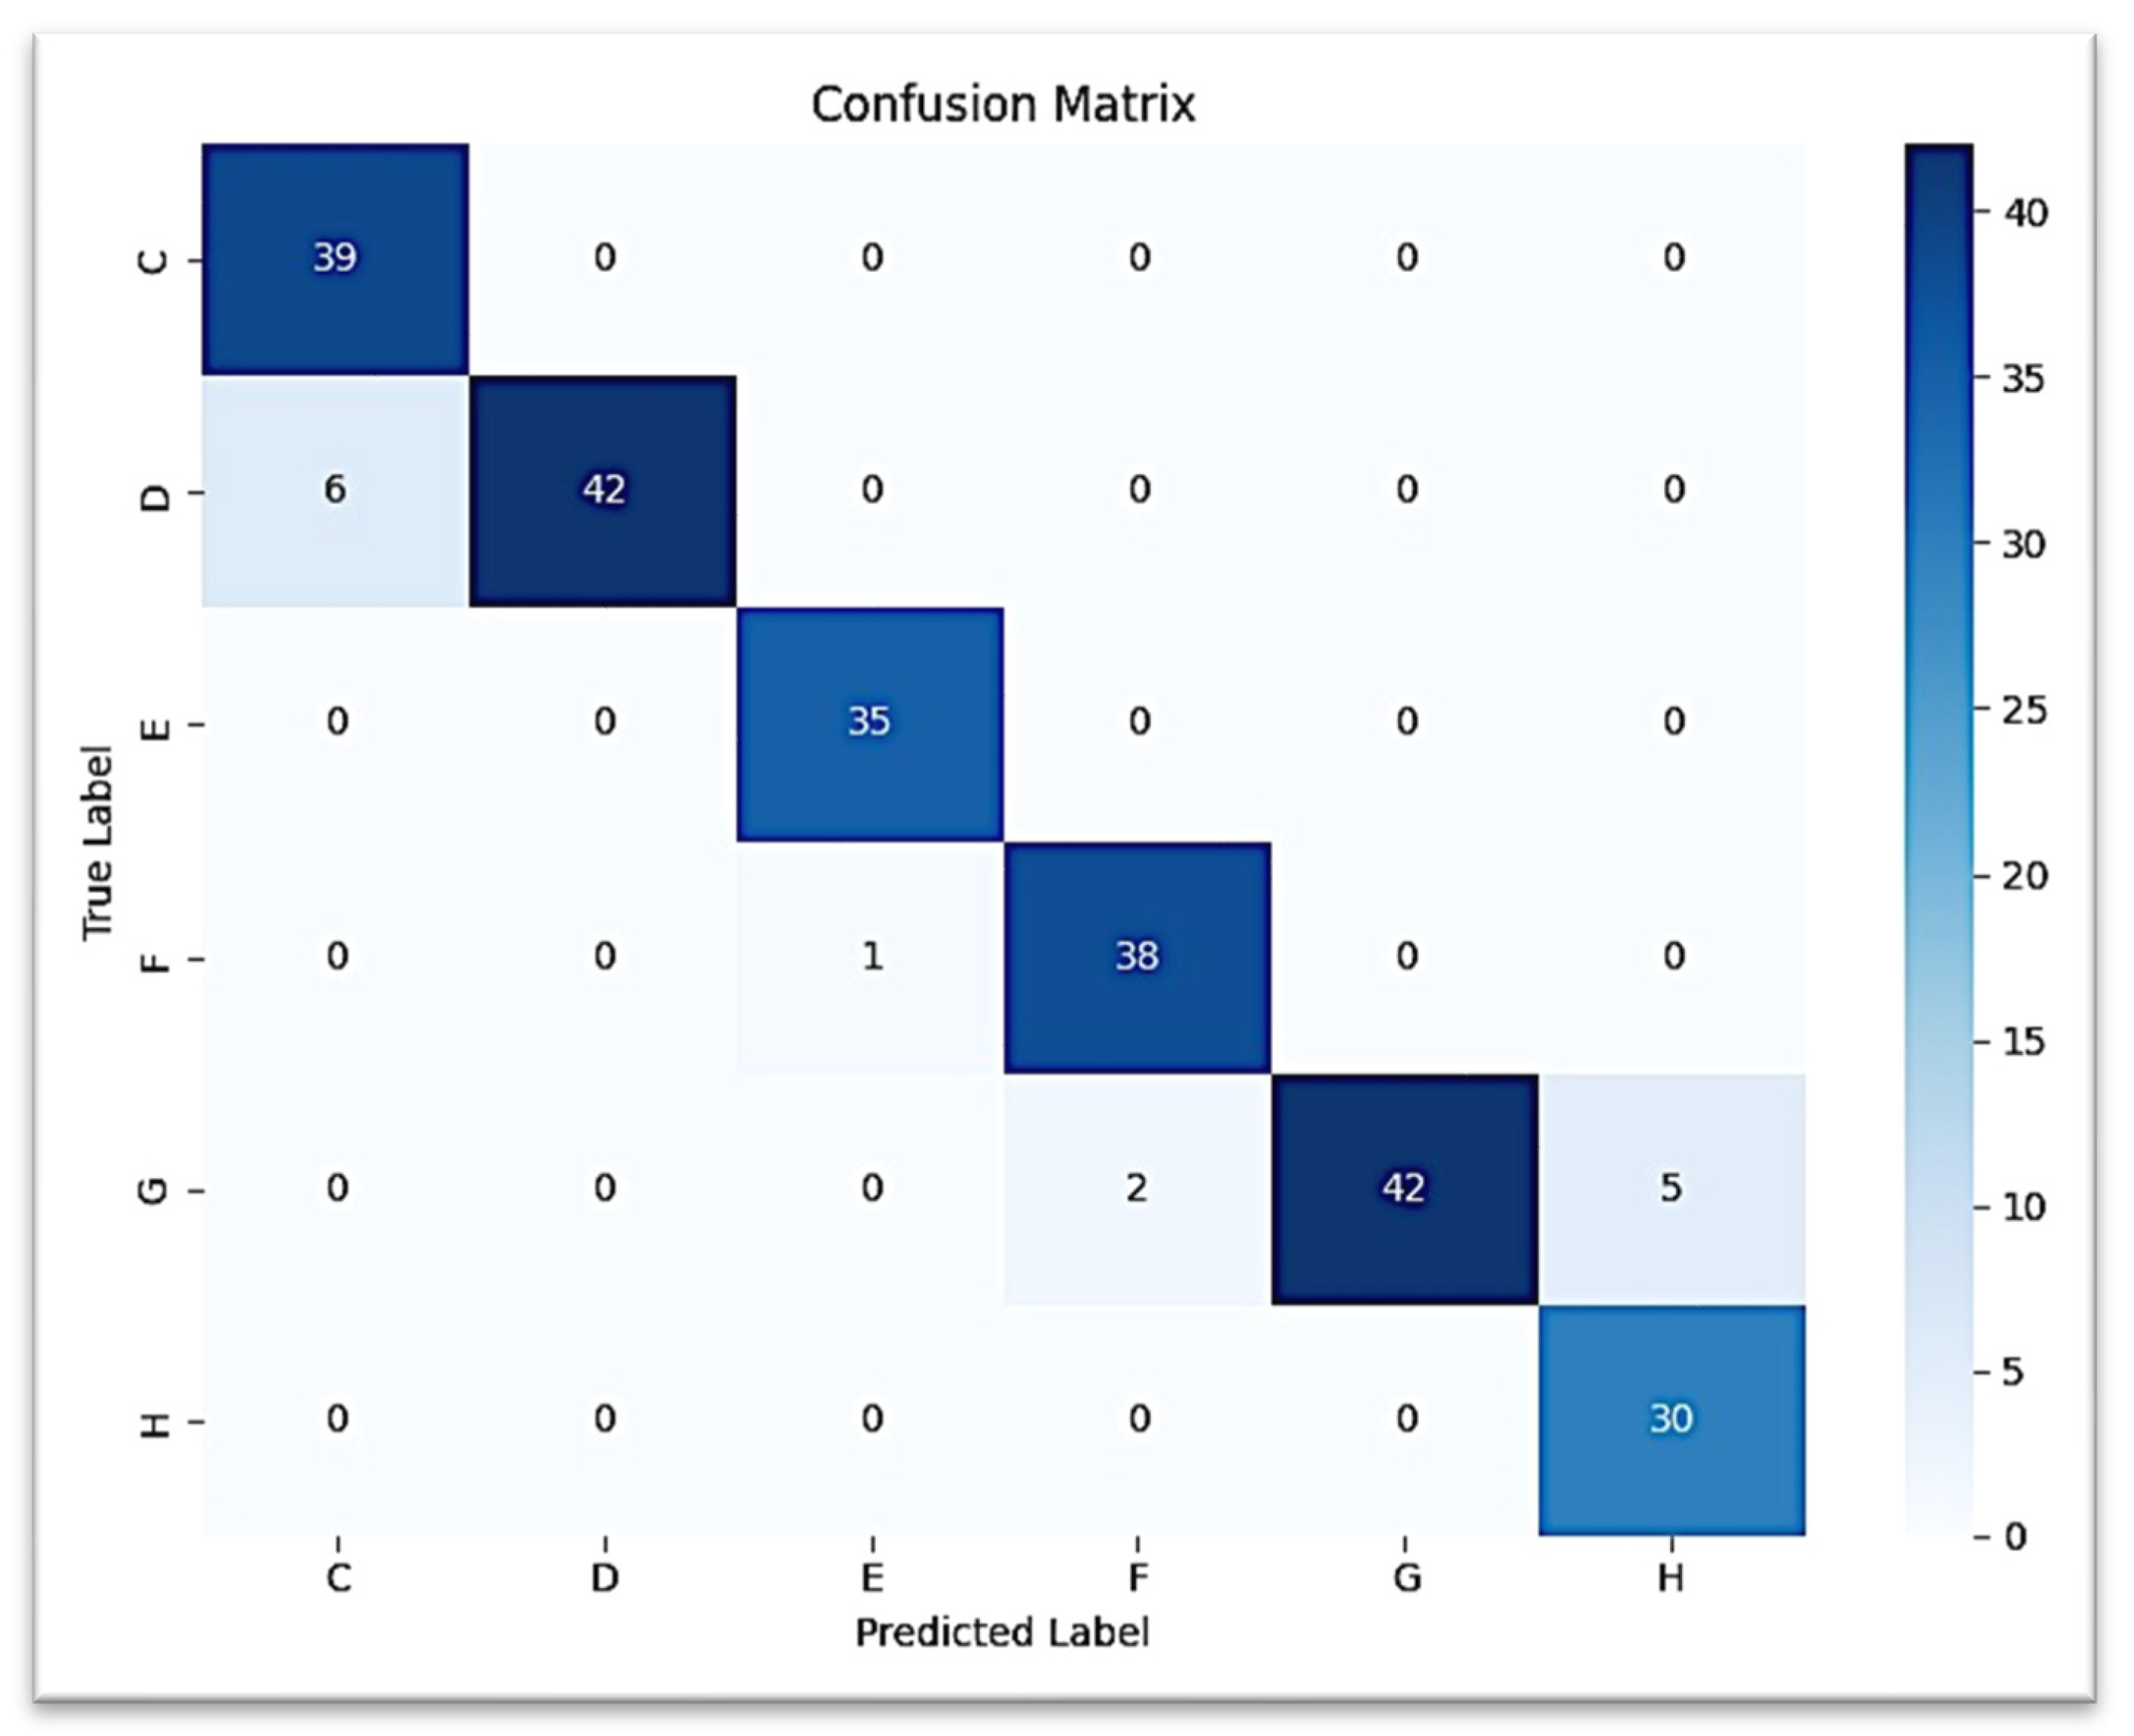

3.2. Prediction of Lower Canine Based on Second Molar

The second CNN model predicting the development of the lower canine from the second molar ROI provided a test accuracy of 97.50% (0.975 weighted F1-score). Classification was perfect (F1 = 1.00) for stages C, D, and E. Stage F was predicted with high performance (precision = 0.95, recall = 1.00, F1 = 0.97), while stage H had lower precision (0.90) but retained perfect recall. Confusion occurred most often between stage G and stage H, with very few G samples classified as H.

The confusion matrix for canine prediction graphed in

Figure 7 shows that almost all of the strong diagonal elements indicate the correct stage predicted stage. A similar multi-class ROC curve (

Figure 8) suggests that the model is robust to all stages of canine development (AUC = 1.00 for all but G stages, which scored AUC = 0.99).